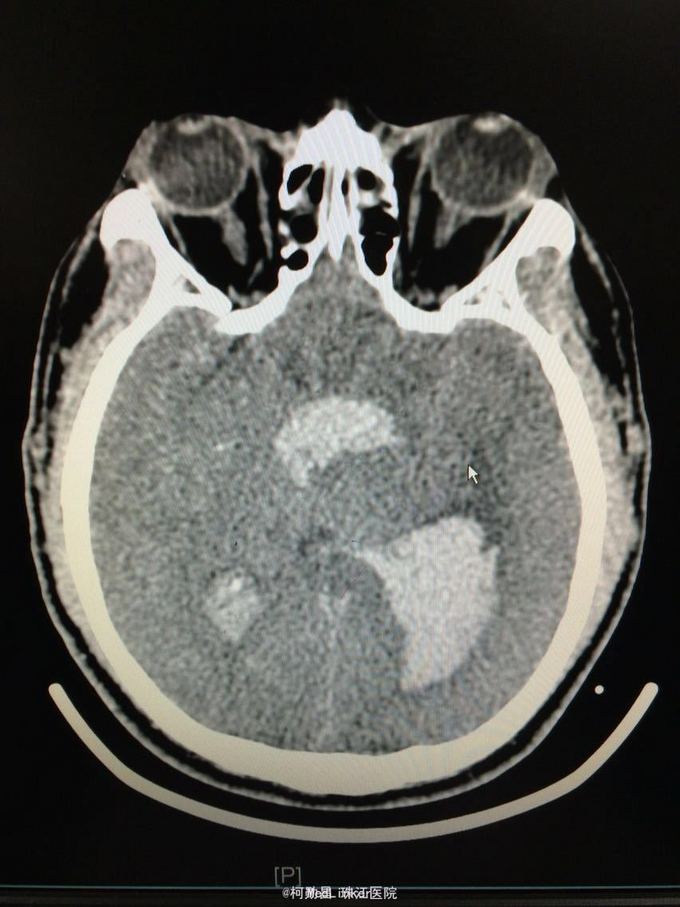

主诉:突发意识障碍4小时 病史:患者57岁男性,入院前一天晚上突发意识不清,伴呕吐胃内容物多次,无肢体抽搐等,随即由家人呼叫120送至我院,急诊行头颅CT提示左侧基底节区出血破入脑室。既往高血压病史10多年

查体:神志不清,双侧瞳孔散大,对光反射消失,四肢肌张力正常,肌力无法检查 辅助检查:头颅CT提示左侧基底节区出血破入脑室

诊断:左侧基底节区出血并破入脑室 处理:急诊行侧脑室钻孔外引流术,术后并予积极抢救,最终抢救无效死亡